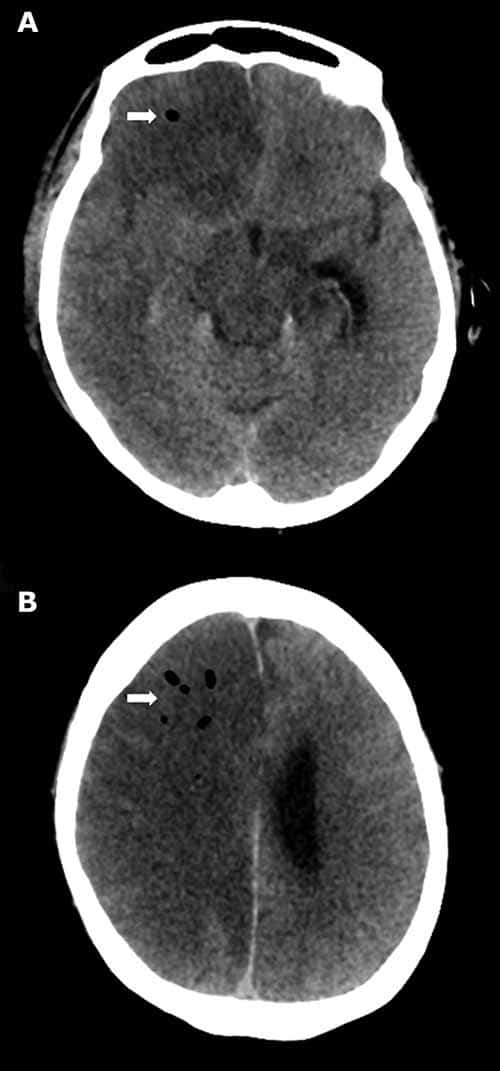

Arterial gas embolism is less common, but more poorly tolerated than venous gas embolism. While air may be introduced primarily into the arterial system, all venous gas emboli have the potential to secondarily involve the arterial system (i.e., paradoxical emboli). Paradoxical emboli may arise via intracardiac shunts (e.g., probe patent foramen ovale, atrial septal defect), intrapulmonary shunts (e.g., arteriovenous malformation or fistula), or by simply overwhelming the normal physiologic mechanisms preventing arterial embolism (e.g., filtration by pulmonary capillaries). Arterial gas emboli may obstruct end arteries; while gas emboli to viscera or skeletal muscles are generally well tolerated, the heart and brain are particularly vulnerable to hypoxia. Gas embolization to coronary arteries may cause ischemia/infarction, dysrhythmias, cardiac failure, or arrest. Cerebral gas embolization may result in stroke, seizures, unconsciousness, and impairment of the respiratory/circulatory centers (Figure 24-6).

If gas embolism is suspected at autopsy, radiography or CT prior to prosection is strongly encouraged. Scenarios that may suggest gas embolism are recent traumatic injury to the thorax, head, or neck, sudden death following a therapeutic or surgical procedure, and recent delivery of child or abortion. External examination findings supportive of fatal air embolism include subcutaneous emphysema and crepitance. There may additionally be marbling, congestion, and/or petechiae that is particularly prominent superiorly (e.g., in the skin of the face, neck, or chest). Chest radiography is not as sensitive as CT and can appear normal in cases of smaller venous gas embolism; with larger volumes, radiolucency (gas) may be appreciated in the main pulmonary artery, right heart (the so-called “C” sign), and hepatic veins (Figure 24-7). CT, by contrast, affords for detection of even small amounts of gas in soft tissues or anatomic cavities. As decomposition can lead to postmortem gas production soon after death, familiarity with typical postmortem gas distribution patterns and/or gas chromatographic analysis may prove necessary in order to distinguish antemortem gas embolism.